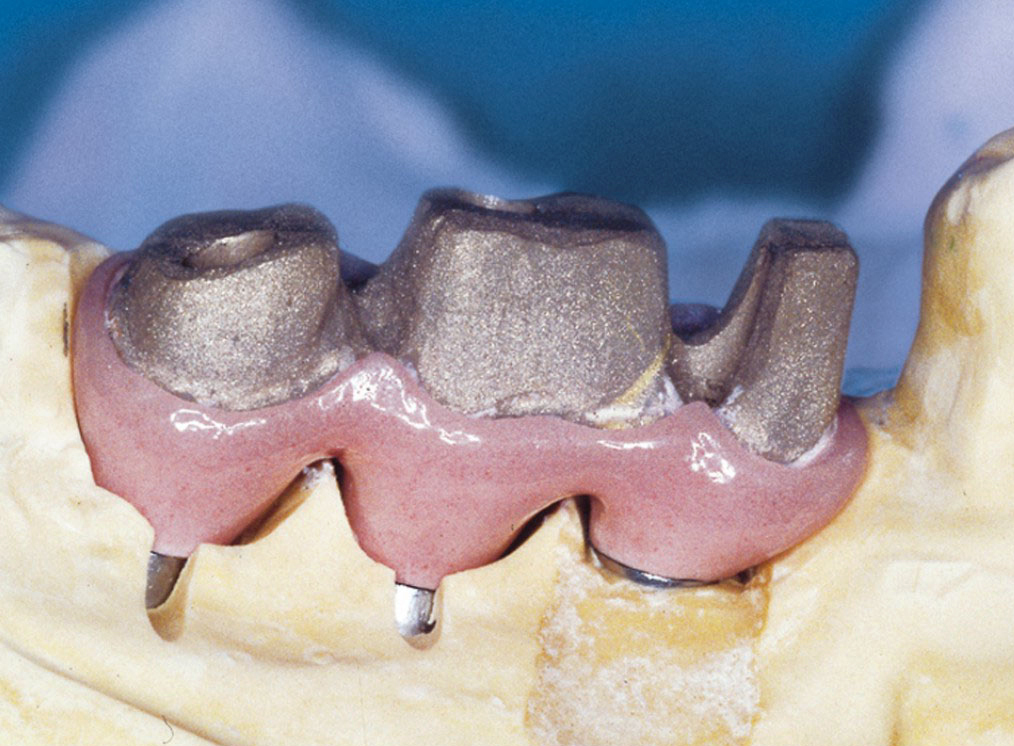

Protetické řešení může být pomocí můstku, který je kotvený na implantátech nebo pomocí jednotlivých korunek na implantátech.

V zásadě je možné do těchto můstků zařadit i přirozené zuby, zejména pokud je potřeba tyto zuby ošetřit proteticky – korunkami. Korunky nebo můstky mohou být na implantáty nacementovány nebo přišroubovány.